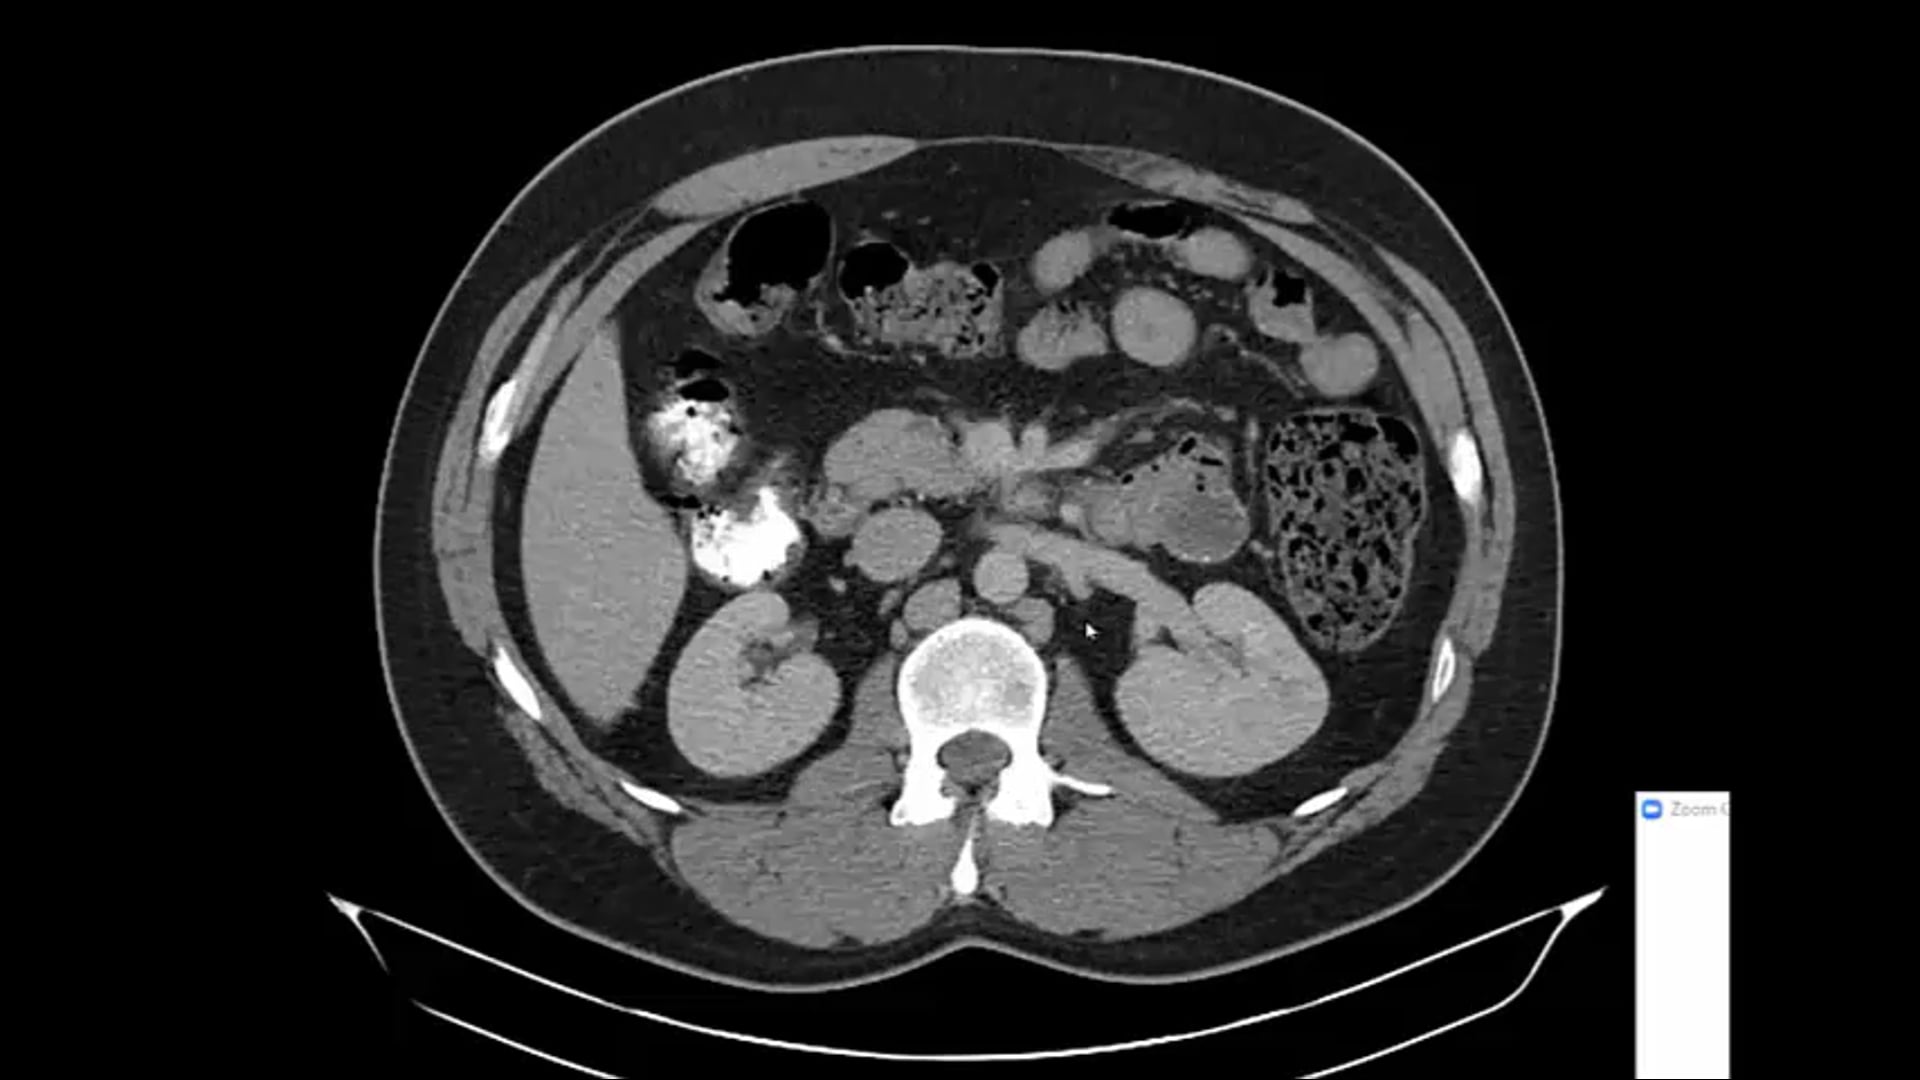

02/25/21 - Dr. Ronald Chen - Radiation Oncology - GU US

Renal cell CA, recurrent renal cancer, kidney mass, SBRT, small bowel dose constraints, bladder management during treatment, boost dose,